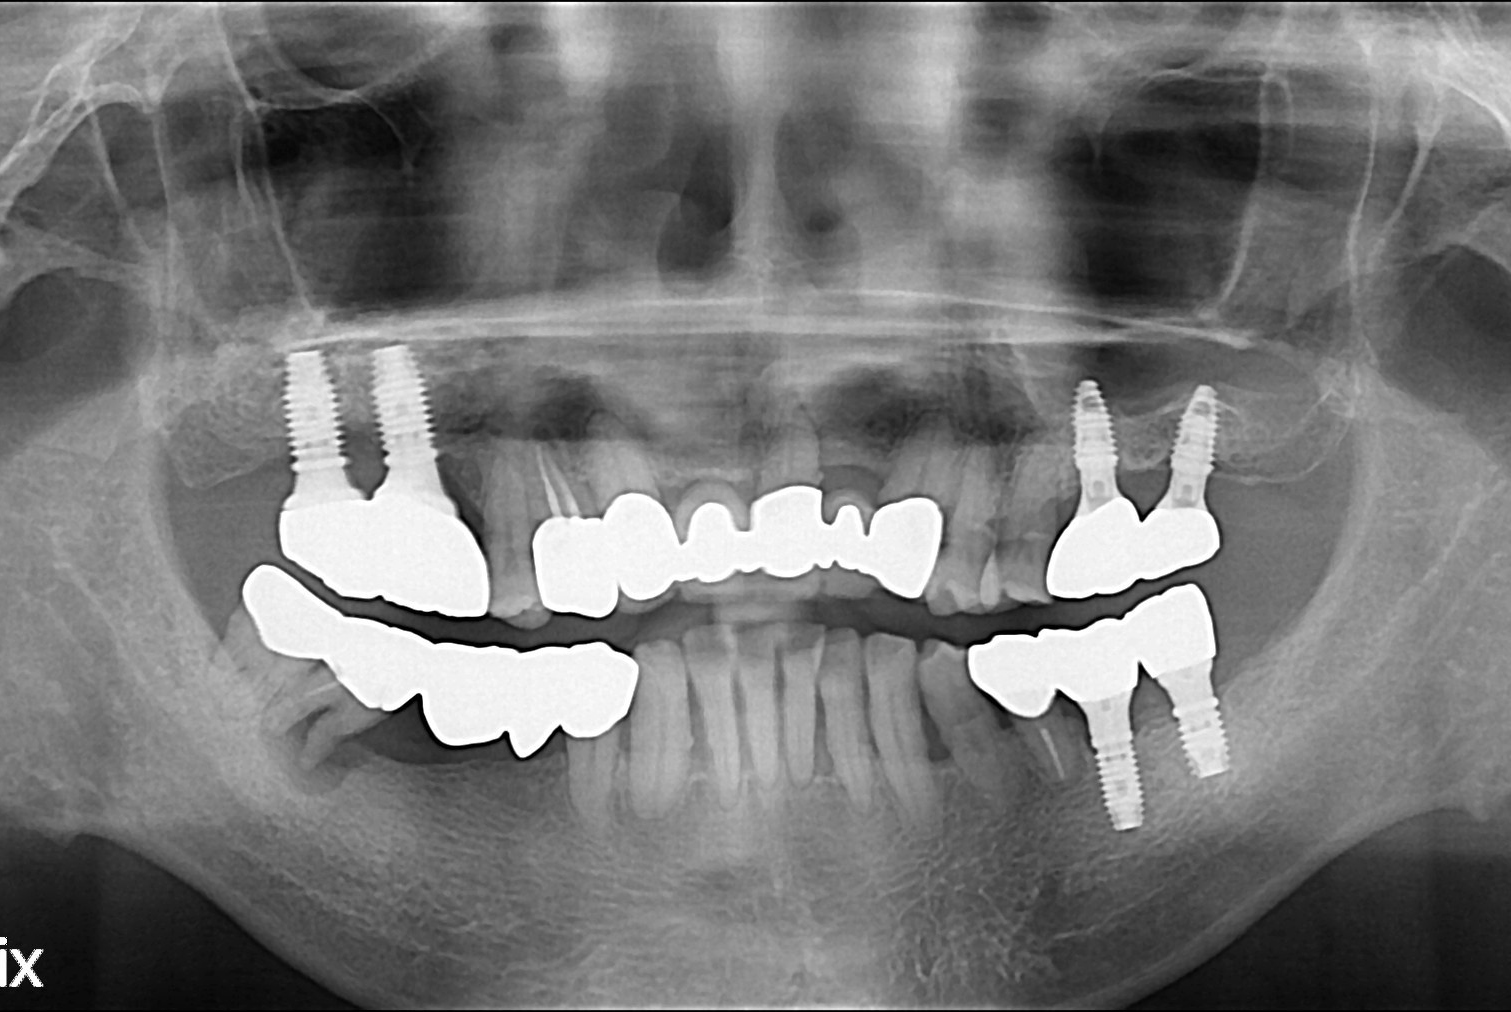

치료전 : 2017-05-25

치료후 : 2017-07-31

세종치과는 많은 환자와 다양한 케이스를 바탕으로 항상 편안한 임플란트 수술을 제공하고자 노력하고,

오래동안 튼튼히 쓸 수 있는 임플란트 수술을 가장 큰 목표로 삼고 있습니다